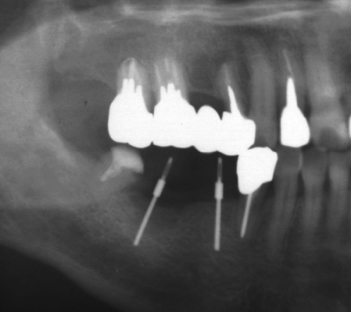

6.CTキャリパーを使い骨壁の厚さを実測する

適切な角度や深さまでパイロットホールが形成されたと判断された場合、CTキャリパーを使い頬側および舌側の骨壁の厚さを実測する。

8.φ1.0mm×10mm~12mmの試適用ガイドを挿入し、

パノラマレントゲン撮影にてパイロット窩を評価する。

9.パイロットホールが適切と確認されたら1サイズ太いドリルにステップアップする

その後、順次CTキャリパーを使い実測を続けながら安全を確保しつつ最終ドリルまでインプラントホールを形成する。

10.最終インプラントホールの骨壁の厚さを実測しフィクスチャーを埋入する

インプラントホールの形成が終わったと判断できたらCTキャリパーにて骨壁を実測し最終の安全確認ができた時点でフィクスチャーを埋入する。

11.フィクスチャーの埋入をパノラマレントゲン撮影にて確認する

フィクスチャーが正しく埋入されたことをデンタルやパノラマレントゲンにて確認する